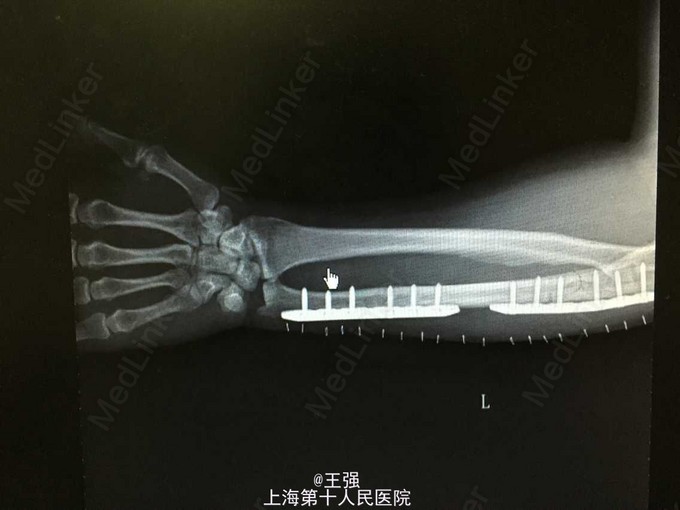

诊断:1.尺骨骨折(左,近端及远端) 2.高血压 治疗:入院后完善相关检查,控制血压,排除手术禁忌症后行骨折切开内固定术,术顺,术后予以抗炎、补液及对症治疗。

随访讨论:患者出院时一般情况可,无发热,心肺听诊无殊,患肢伤口愈合好,无肿胀及渗出,患肢血运感觉可,嘱一个月后门诊复查。